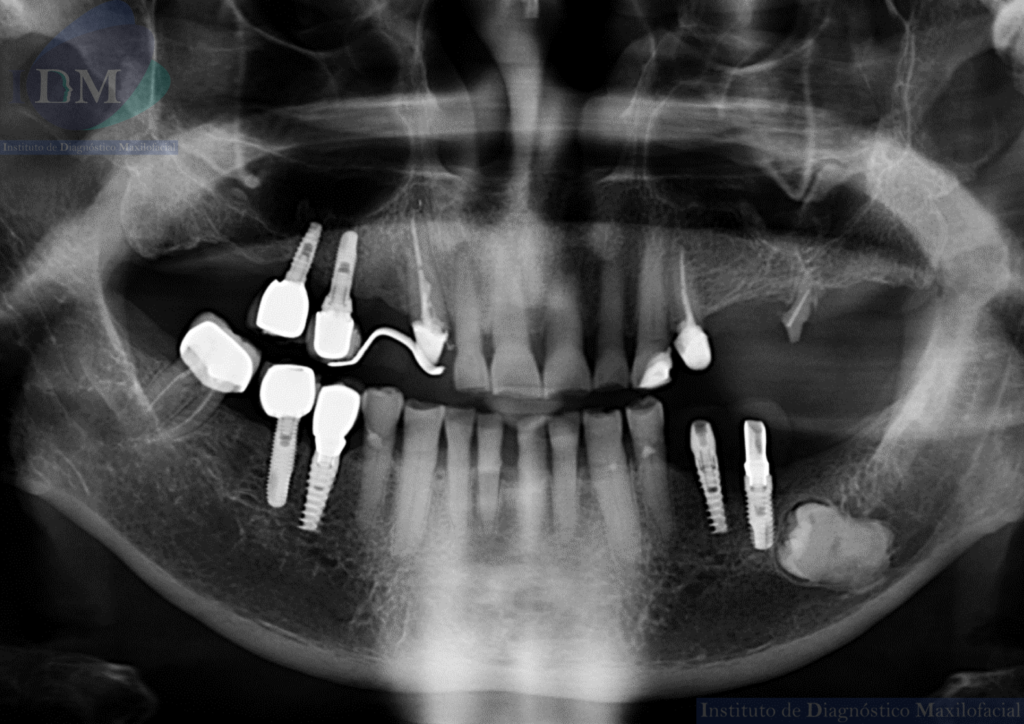

A la evaluación de la radiografía panorámica se evidencia reabsorción ósea alveolar bimaxilar, edéntulo parcial bimaxilar y presencia de múltiples implantes con prótesis sobre implantes así como tratamientos restaurativos. Siendo lo más destacado una molar retenida en cuerpo mandibular izquierdo, la cual esta mesioangulada.

Siendo así que en la tomografía volumétrica de haz cónico se evidencia una hipercementosis radicular, con los segmentos radiculares contactando con el conducto dentario inferior. Finalmente se evidencia un borramiento del espacio del ligamento periodontal compatible con anquilosis dentaria.